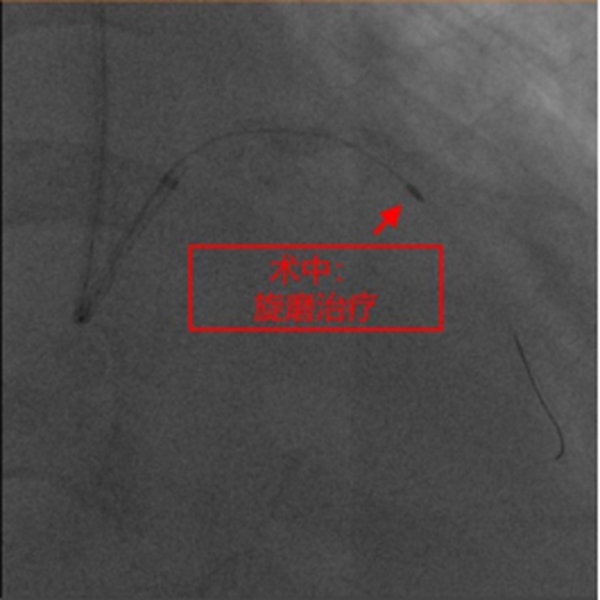

在征得患者及家屬同意,做好充分術前準備的情況下,冠脈介入團隊在冉擘力主任帶領下,按計劃給患者實施了血管內超聲(IVUS)指導下經皮冠脈旋磨+Shockwave沖擊波球囊碎裂鈣化斑塊及支架植入術,術中團隊克服了一系列困難,最終安全順利地完成了全部介入手術過程,完全碎裂了環狀鈣化斑塊,效果非常滿意,歷時約1個多小時,手術成功,病人安返病房。術后患者胸悶、氣短明顯緩解,對治療效果十分滿意。

冉擘力主任介紹,冠狀動脈斑塊旋磨術是采用橄欖形的帶有鉆石顆粒的旋磨頭,根據“差異切割”的理論選擇性地祛除鈣化或纖維化的動脈粥樣硬化斑塊,為后續介入操作打開一條“通道”,已在臨床開展近30年,是治療重度冠脈鈣化病變的一種利器。但是,冠狀動脈斑塊旋磨術有其局限性,對于極度迂曲、成角的鈣化病變發生旋磨頭嵌頓和冠脈穿孔的風險較高,而對“緊箍咒”似的鈣化環依然無能為力,并且單純旋磨后獲得血管腔面積有限。